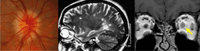

- La anomalía de morning glory con frecuencia se presenta asociada al encefalocele transesfenoidal (Figura 7). Éste también se manifiesta junto con discos ópticos displásicos y anomalías retinocoroideas infrapapilares en forma de V o de reguero. La enfermedad de Moyamoya es una vasculitis cerebral rara que también se asocia a esta anomalía papilar.

Figura 7. Anomalía de morning glory con encefalocele transesfenoidal asociado

Figura 8. Coloboma

Figura 9. "Vacant disc" asociado a hipoplasia renal (ecografía renal)

- El coloboma del nervio óptico (Figura 8) o el estafiloma no suele acompañarse de alteraciones del sistema nervioso central, con lo que no estaría indicada ninguna prueba de neuroimagen.

- Un caso particular es el de disco óptico vacío (“Vacant disc”). Se presenta de forma bilateral con discos excavados y anomalías en el origen de los vasos centrales en el contexto del síndrome papilorrenal. No requiere neuroimagen, pero sí la realización de una ecografía doppler renal para el estudio de anomalías estructurales en el aparato urinario como la hipoplasia renal (Figura 9).